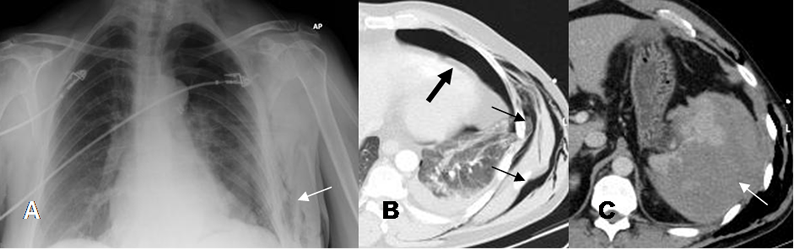

Fig 26. Neumotórax.

A: Rx PA. Enfisema celular subcutáneo, lo que hace sospechar fractura costal y neumotórax.

B: TAC axial. Enfisema celular subcutáneo (Flechas delgadas) y neumotórax. (Flecha gruesa).

C: TAC axial. La fractura costal ocasiona adicionalmente gran contusión esplénica.